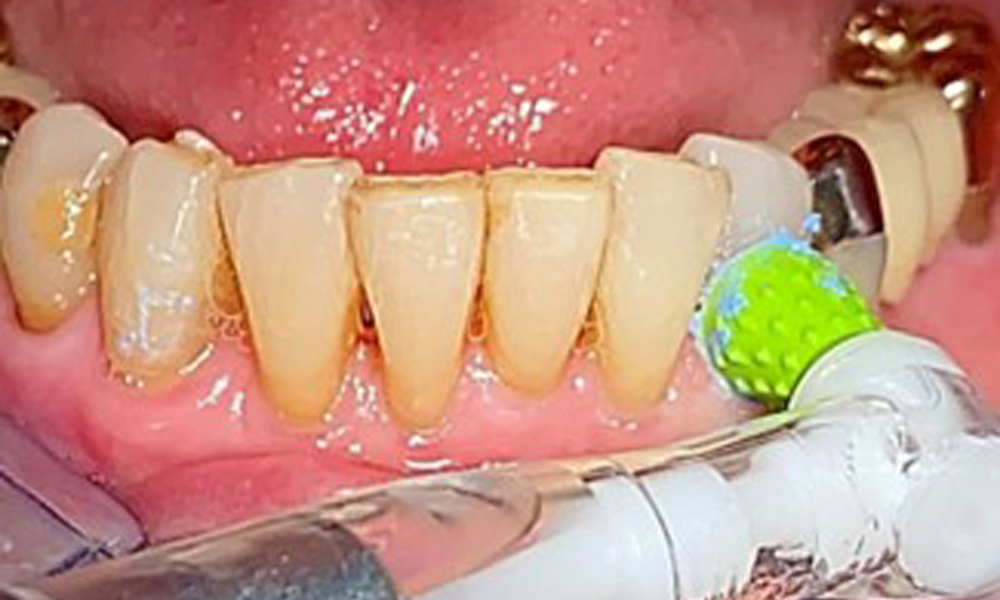

Occlusal view of the mandible.

Fig. 4: Occlusal view of the mandible.

The dental findings are as follows: Combined removable implant and tooth-supported telescopic prostheses on implants 15, 13, 21, 23, 24, 25 and tooth 11 (Fig. 1, Fig. 2, Fig. 3). The patient was fitted with a fixed mandibular denture. Adequate bridges were present over 37 to 34 and 45 to 47 (Fig. 4), the crown margins were intact and there were no active caries. A composite filling with a marginal gap was present on tooth 43. There was mandibular gingival recession, exposing 1 to 3 mm of root surface. This also applies to 11.

An air polishing system should be used with low-abrasive powder to remove biofilm from the restoration margins, interdental areas and implant surfaces (Fig. 12). Selective polishing (Fig. 13) should be used to smooth any less sensitive areas, as this decreases bacterial reattachment (9).

Selective polishing of tooth 33 (Proxeo Twist, W&H, shown here)

Fig. 13: Selective polishing of tooth 33 (Proxeo Twist, W&H, shown here)